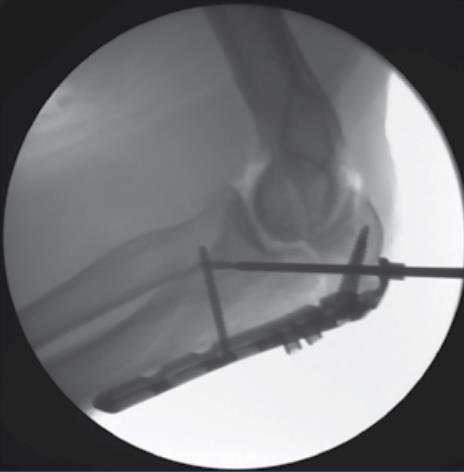

• Fracture Reduction

• reduce the fracture by levering the shaft of the plate to the distal fragment

• confirm fracture reduction and plate alignment using fluoroscopy

• Fluoroscopic Confirmation

• repeat steps past two steps for the remaining olecranon screw hole using a 3.5mm Multi-Thread Locking Screw

• confirm proper plate positioning, fracture reduction and screw lengths using fluoroscopic imaging